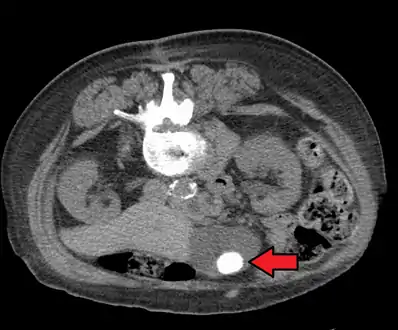

Mixed (brown pigment stones) typically contain 20–80% cholesterol (or 30–70%, according to the Japanese classification system).[36] Other common constituents are calcium carbonate, palmitate phosphate, bilirubin and other bile pigments (calcium bilirubinate, calcium palmitate and calcium stearate). Because of their calcium content, they are often radiographically visible. They typically arise secondary to infection of the biliary tract which results in the release of β-glucuronidase (by injured hepatocytes and bacteria) which hydrolyzes bilirubin glucuronides and increases the amount of unconjugated bilirubin in bile. Between 4% and 20% of stones are mixed.[3]

Diagnosis is typically confirmed by abdominal ultrasound. Other imaging techniques used are ERCP and MRCP. Gallstone complications may be detected on blood tests.[2]